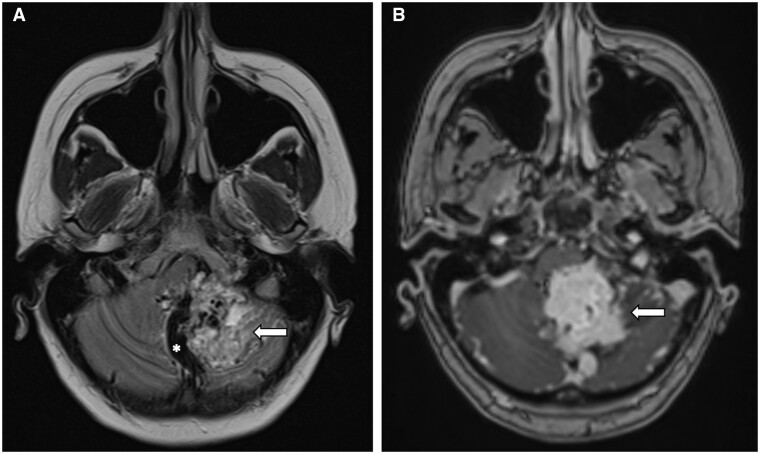

Optic nerve haemangioblastoma (ONH) is an uncommon, benign, non-meningothelial, mesenchymal tumour of unclear origin. Most are associated with von Hippel-Lindau (VHL) syndrome (71%), and only 40 cases have been reported in the medical literature. Most of the patients develop non-specific visual symptoms, including decreased visual acuity and/or loss of visual fields, exophthalmos, trigeminal neuralgia, and retroorbital pain. Optic nerve sheath meningioma and optic nerve glioma are among the differential diagnoses that may be considered in this location. Contrast-enhanced MRI is considered an optimal diagnostic tool, which helps to determine some characteristics that guide towards an adequate diagnosis and treatment. We present a 42-year-old patient with a history of VHL syndrome in whom a cerebellar lesion and optic nerve lesions were evidenced, and we did a review of the literature and case analysis.